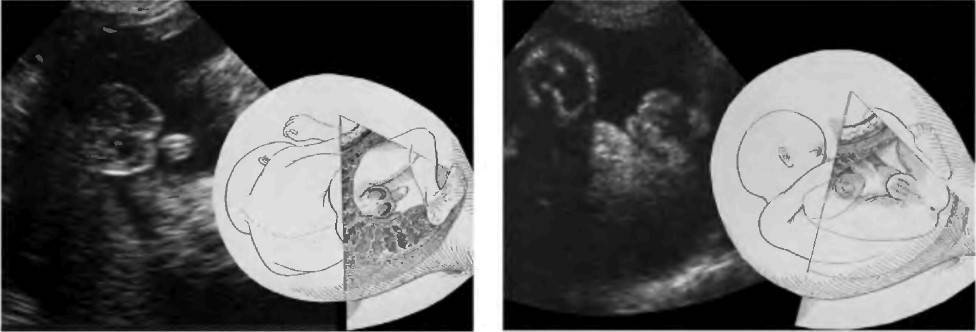

Пол плода в сроке 12-14 недель беременности, как правило, можно оценить на основании величины угла между половым бугорочком и горизонтальной линией, проходящей вдоль спинки плода. Если угол между этими структурами больше 30 градусов, то имеется высокий шанс развития ребенка мужского пола. Если же угол меньше 30 градусов или равен нулю, то скорее всего развивается девочка. Достоверность определения пола ребенка по такой методике при ее четком выполнении достигает 98,0% в 12 недель беременности.

Определение пола по величине угла. Сверху — девочка, снизу — мальчик

На сроке после 14 недель пол плода можно установить на основании визуализации наружных половых органов в области промежности в различных плоскостях сканирования. У мальчиков видны пенис и мошонка, у девочек большие половые губы. Иногда увеличенный клитор может имитировать половой член. Улучшает точность диагностики использование УЗИ с трехмерной реконструкцией (3D-УЗИ), которое позволяет более точно рассмотреть гениталии ребенка.

Эхограмма и схематическое изображение определения пола плода